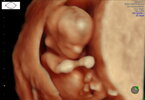

Ja już po wizycie. Maluch rośnie jak na drożdżach

tydzień temu 4.3 cm dziś 6.3cm. Nadgonił/a różnicę tych 3 dni z om, które zmieniła moją ginekolog.Z nóżkami 10.80cm szczęścia ❤❤

Ale maluch kręci się bardziej niż nasza mała w poprzedniej ciąży

. Wszystko jest póki co dobrze, lekarz mimo tego że gbur

to wszystko dokładnie omawiał. Bardzo długo sprawdzał serce,przeplywy.

Nie pytaliśmy lekarza o płeć, na zdjęciu jeszcze nic nie widać